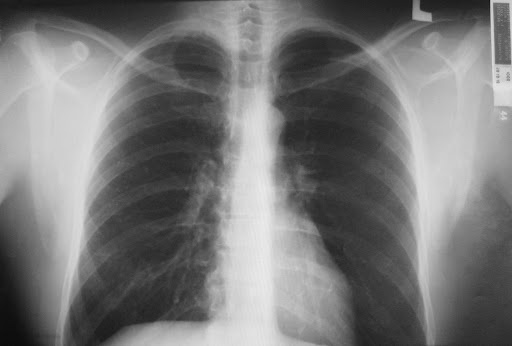

Рентген так же назначается только при подозрении на пневмонию, так как бронхит на нем не виден.

Рентген-признаки бронхита